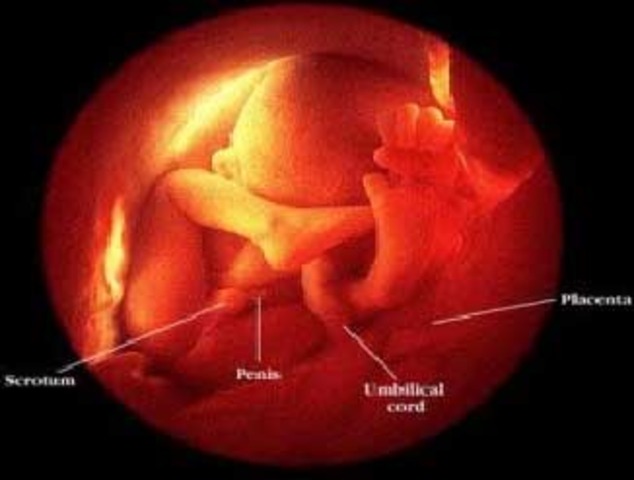

• week 12

week 12

The fetus is now about 2.5 inches (6cm) length and weighs about 0.7 ounce (20 g).

The feet are almost half an inch (1cm) long.

The fetus starts moving spontaneously.

The face is beginning to look like a baby's face.

The pancreas is functioning and producing insulin.

Fingernails and toenails appear.

The baby can suck his thumb, and get hiccups.